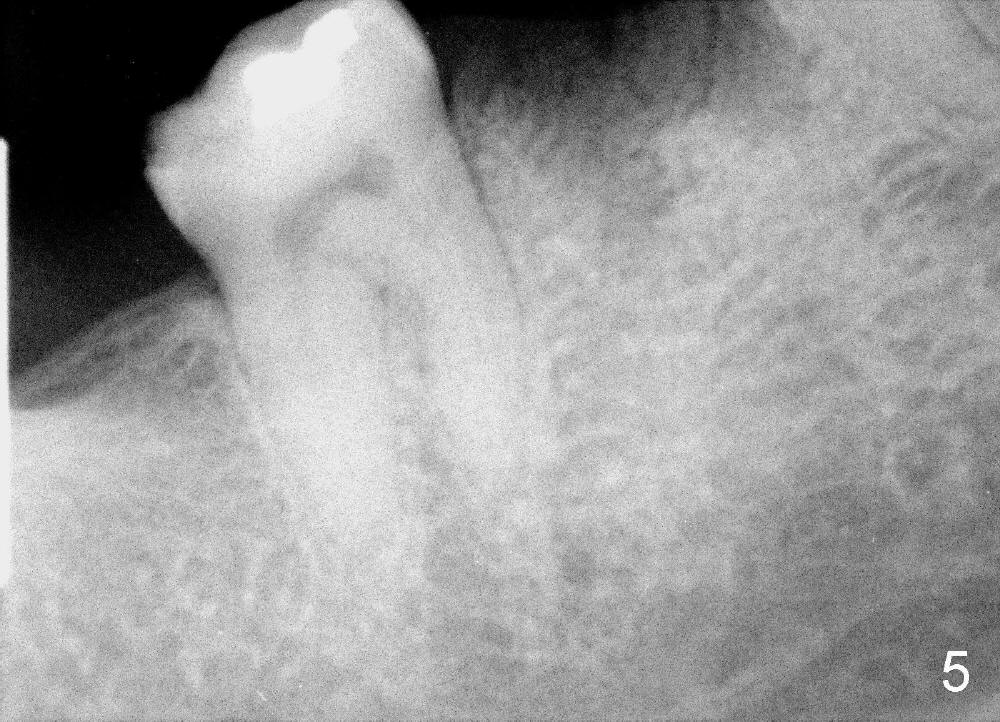

A 38-year-old lady agrees to have implant placement 7 years after loss of the crown of the lower right first molar (Fig.1,2). When the tooth is extracted, the septum is found to be low (Fig.3,4). To confirm it, a PA is taken (Fig.5). To initiate an osteotomy in the septum, it is trans-sectioned with thin osteotomes as shown in Fig.4 insert (black line). A 2 mm pilot drill is placed in the septum (Fig.6: P). The osteotomy is enlarged by 2.5-4.0 mm reamers (Fig.7,8), followed by insertion of 6x17 mm tapered tap at the depth 14 mm (Fig.9). The osteotomy is further enlarged by 4.5 and 5.0 mm reamers. A 6.0x14 mm one piece implant is placed initially. The trajectory is not ideal. A 6.0x14 mm one piece implant is placed initially. The trajectory is not ideal. The implant is removed from the osteotomy partially and reinserted with improved trajectory (Fig.11, compare to Fig.10 (red line)). Primary stability is high. There is not much bone mesiodistally so that the trajectory is easily changed in that direction. After abutment preparation, mixture of autogenous bone (harvested from reamers) and allograft is placed in the residual mesial and distal sockets (Fig.12). To contain the bone graft, an immediate provisional is placed (Fig.13 P). The occlusal plane of the provisional is significantly lower than that of the adjacent teeth to avoid micromovement of the implant. The patient is advised to eat soft food on the left side. Six days postop, the patient returns for prophy. The provisional is removed; the bone graft appears to be incorporating into the socket (Fig.14). After recementation, the provisional remains in place for 3.5 months; PA shows increased bone density in the mesial and distal sockets (Fig.15, compare to Fig.5,11). Due to insurance coverage, the patient defers fabrication of definitive restoration for at least 7 months. The immediate provisional is finally lost 8.5 months postop: the gingiva attaches to the 1-piece implant (Fig.16), while the density of the mesial socket increases (Fig.17 *) with formation of the cortex (lamina dura) coronally (v). Before the provisional (Fig.18 P) is removed for cementation of the definitive restoration, black shadow (*) is noted over the buccal gingiva. It is partially due to buccal placement (Fig.19) and partially due to buccal atrophy over a period of 10.5 months postop. How to prevent buccal placement? Positioning the first pilot drill in the septum buccolingually is a key. Eleven months post crown (Fig.20 C) cementation, the black shadow remains, but there is no tenderness. If the implant threads are immediately underneath the periosteum, there is tenderness.

CBCT taken 15 months post cementation shows that the implant is buccally placed (Fig.21 B), associated with possible postop buccal plate resorption (as compared to Fig.23 (coronal section of the site of #19). The buccal plate is not only thinner than the lingual one, but also concave (Fig.22 <). The tooth center (i.e., septum; Fig.23 T) is more buccally located than the center of the basal bone (B). Considering the denser bone lingually, the initial osteotomy should be more lingually (^). If the implant develops infection, it will be replaced by a more lingually placed implant (Fig.24 green).